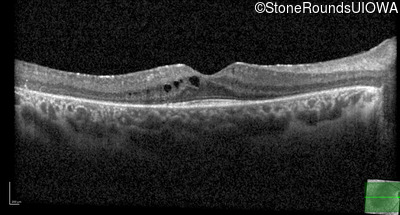

Age at visit: 10 years